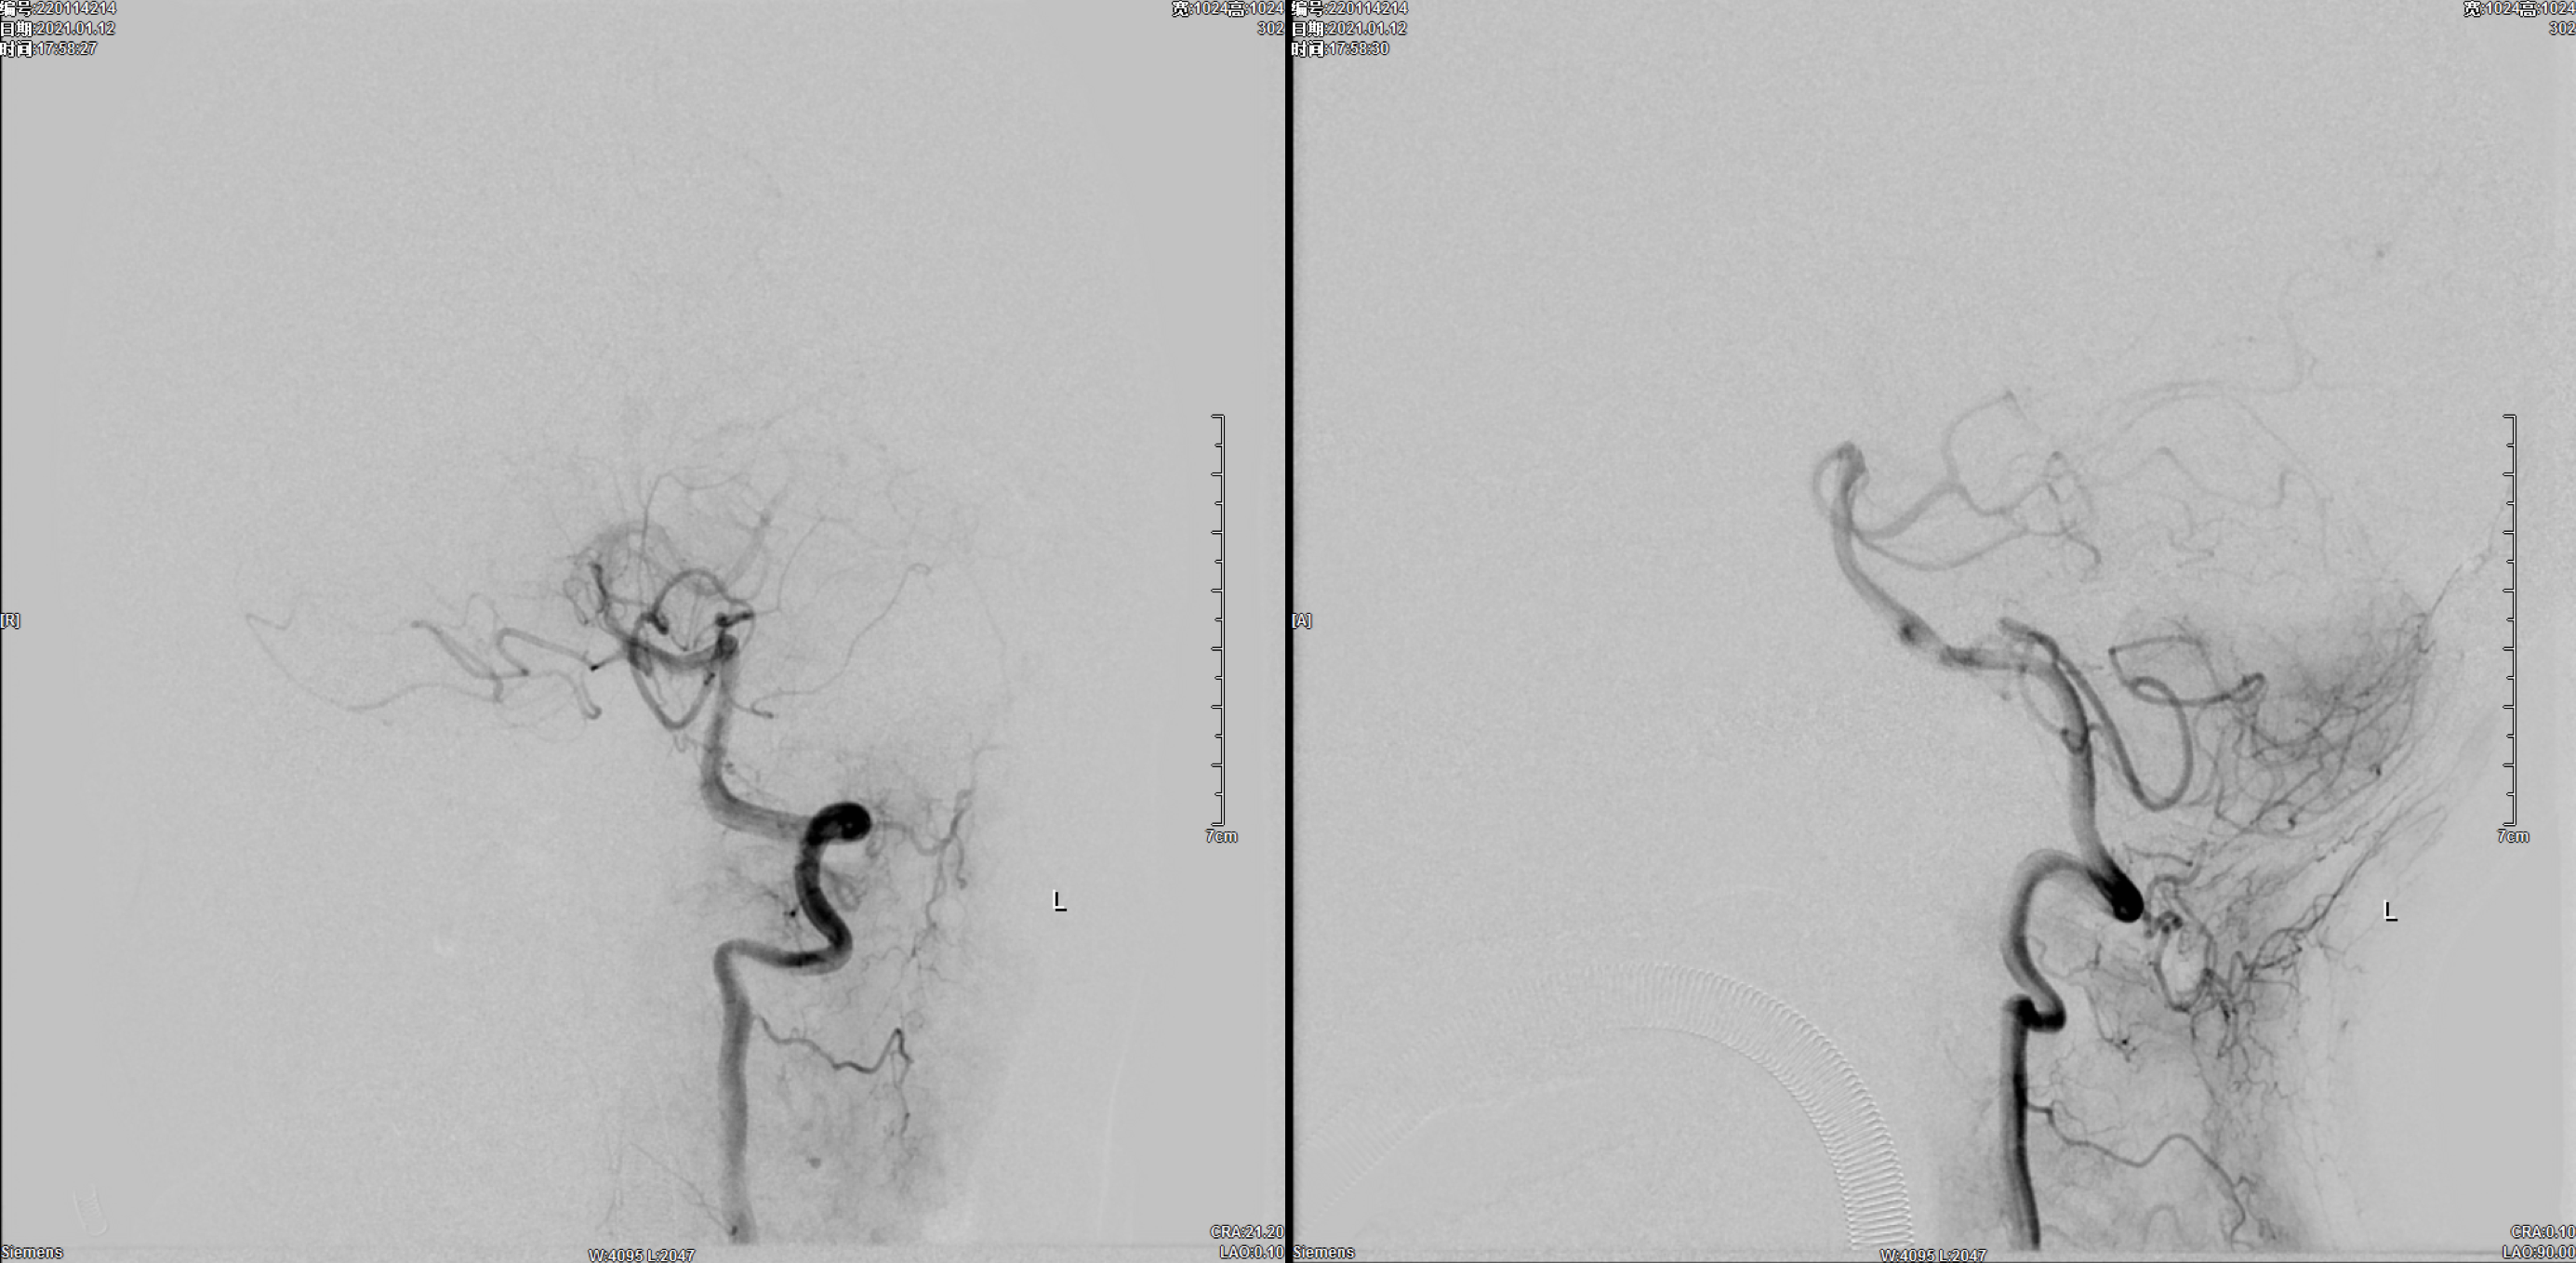

左侧颈内动脉正侧位造影:未见明显异常!

左侧颈动脉正侧位造影:未见明显异常!

右侧颈动脉正侧位造影:右椎动脉发育纤细!

右侧颈内动脉正侧位造影:后交通动脉瘤,后交通动脉发育粗大!

术后即刻正位造影:动脉瘤栓塞满意!

术后即刻侧位造影:动脉瘤栓塞满意!